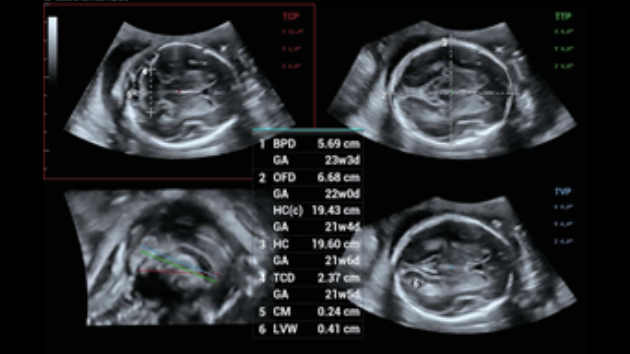

Ongeacht of u werkzaam bent in een ziekenhuis of kliniek, of uw vaardigheden aanscherpt op het gebied van algemene beeldvormingstoepassingen, vrouwengeneeskunde of cardiovasculaire specialismen, in deze serie vindt u zeer krachtige hulpmiddelen waarmee u aan kop kunt blijven.